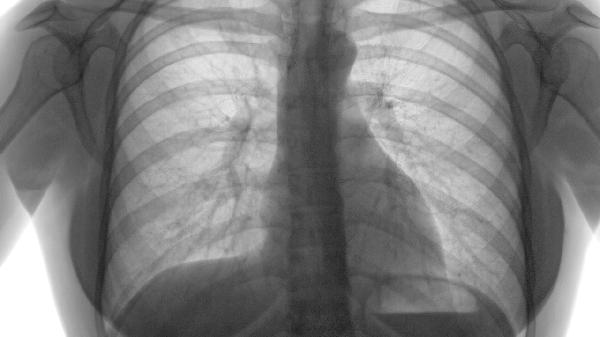

肺气肿的本质是肺泡结构破坏,属于非感染性病理改变。其核心机制为蛋白酶与抗蛋白酶失衡导致肺组织损伤,与病毒、细菌等病原体无关,因此不会通过飞沫或接触传播。

传染性呼吸道疾病如肺结核、流感等具有特定病原体和传播途径,而肺气肿是终末细支气管远端气腔永久性扩张,两者发病机制存在本质区别。